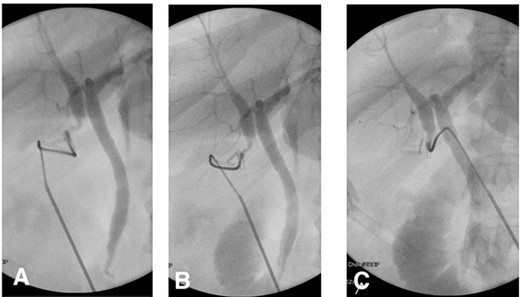

The patient’s postoperative course was uneventful, the drain was removed on postoperative day three. Prior to discharge, a postoperative computed tomography (CT) cholangiogram was performed which revealed the duplicated CHD terminating within the region of the cholecystectomy clips with a communicating aberrant extrahepatic duct (Fig. 3). Subsequently, histopathology had shown chronic cholecystitis with cholelithiasis.

(A) Axial CT image showing the cholecystectomy clips at the base of a duplicated CHD with the corresponding CHD on the medial aspect. (B) 3D reconstruction demonstrating the CHD duplication with a single distal draining CBD.